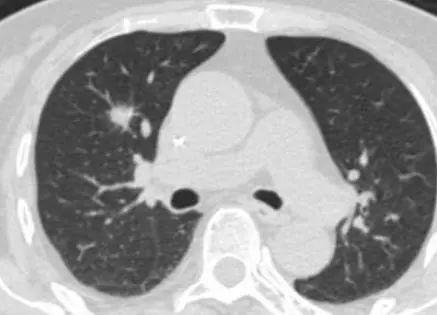

一年前,江阿姨复查体检时发现右肺上叶前段临近肺门有一孤立性结节,为边缘毛糙的实性结节,大小约为10×11毫米,医生考虑为原发或转移性肿瘤。家人赶紧带着江阿姨前往市区三甲医院就诊,辗转多家医院后,由于患者年纪大,加之合并症多,手术复杂且风险高,均未被收治。

近日,江阿姨再次到来到嘉定区中心医院血液内科治疗,得知江阿姨的诉求后,医院血液内科马上联系了胸外科李建新主任团队一同展开会诊。“结合患者CT考虑肺癌,且有手术指征。如果不限期手术,恐怕病情进展太快而失去最佳治愈机……”李建新表示。